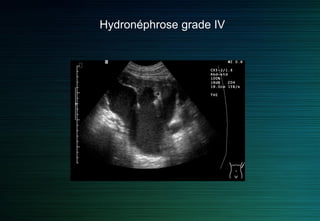

On différencie quatre grades d’hydronéphrose sur des critères échographiques

Grade 4 : plus de parenchyme visible.

Hydronéphrose grade IV